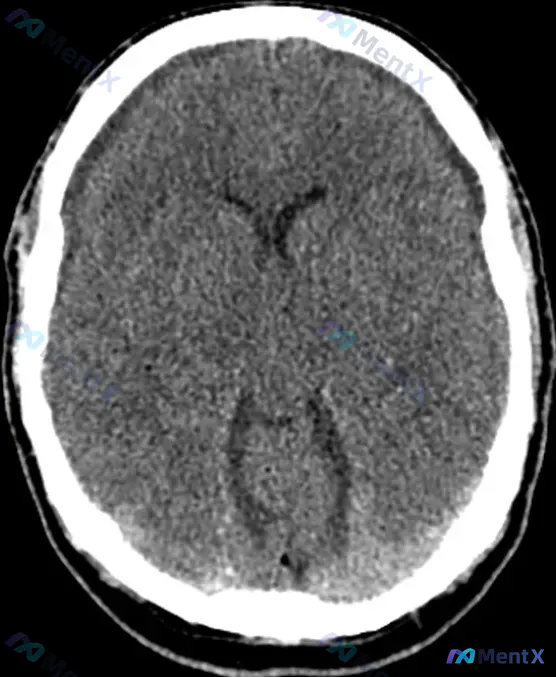

今天看到一份影像资料有点感慨——输入明确写了“Bifrontal hypoattenuating subdural collections(双侧额部低密度硬膜下积液)”,但原始影像分析结论却写着“颅内结构未见明显病理改变”。 整理一下这个病例的核心信息和我的分析思路: --- 先理清楚明确可见的“事...